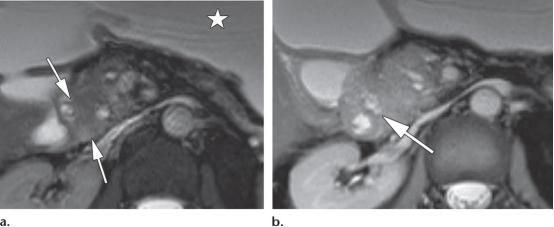

42岁男性,2型自身免疫性胰腺炎

(a图)轴位T2WI示胰腺近端边界不清的等信号肿块样病变(白色长箭头)

(b图)冠状位T2WI示胰管管径变窄,并横穿同一区域(白色长箭头),注意观察胆总管远端的局灶性狭窄(白色短箭头)